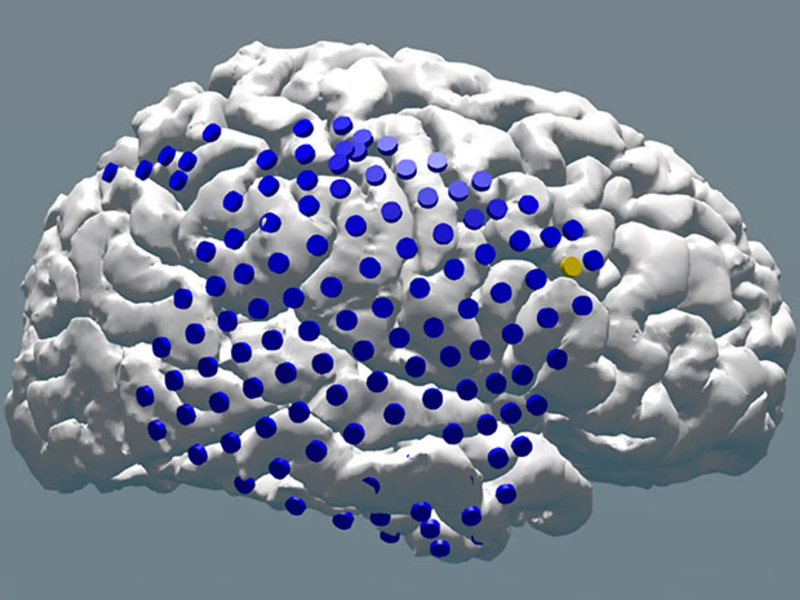

Diagrama de um dos hemisférios de um “cérebro generalizado” estudado no Laboratório de Memória Computacional usando um sistema de aprendizado de máquina, com os pontos de entrada indicados para todo o conjunto de eletrodos (fonte: Universidade da Pensilvânia)

Os testes envolveram 102 pacientes, cada um com cerca de cem eletrodos implantados em diferentes partes do cérebro. Todos eles fizeram um teste padrão de esquecimento de memória, que envolve mostrar uma lista de várias palavras aleatórias por um determinado período de tempo e, em seguida, uma série de tentativas de reproduzir essa lista – em intervalos crescentes. Ao longo do teste, eletrocardiogramas intracranianos (intracranianos) e ECGs foram obtidos dos participantes usando eletrodos implantados, que foram processados ​​em um computador usando um sistema de aprendizado de máquina.

Como resultado, assumindo que o espaço intracraniano em todos os indivíduos é geralmente organizado da mesma maneira, os pesquisadores obtiveram iECG como se de 10 mil eletrodos implantados em diferentes partes do mesmo “cérebro generalizado”. Analisando os padrões característicos (padrões) da atividade cerebral nos estágios de memorização de dados primários, sua subsequente recordação e subsequente esquecimento, o sistema criou um modelo de classificação para essa mesma atividade. A inteligência artificial, ainda que rudimentar, colocou uma mão virtual no estudo do natural!